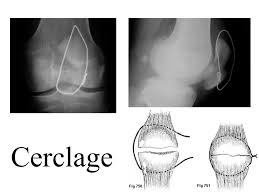

Ci après quelques illustrations de traitement chirurgical :

Cerclage de rotule